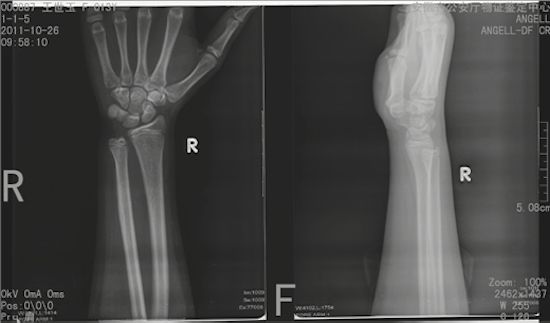

这项技术主要是根据人体骨骼发育中骨骺[注]愈合的程度来进行骨骼生理年龄的判断。骨骺愈合时间自13岁开始自25岁完成,法医“蜀黍”们通过阅读各个年龄阶段人的四肢骨骺愈合程度,得出一个统计学上的多元回归方程。在遇到需要鉴定的案例时,通过被鉴定人骨骺愈合程度特征,代入方程,即可计算出TA的生理年龄了。经过实践验证,被鉴定人22岁以下的情况,鉴定出的生理年龄和其真实年龄只有±1岁的误差哦。

可是,如何观察被鉴定人的骨骺愈合程度呢?因为观测点主要是四肢长骨的两端,所以法医“蜀黍”们的办法是带

被鉴定人去拍摄全身六大关节的X片(关节就是长骨一端对接的地方)。所谓的六大关节就是肩关节(观察肱骨上端和肩胛骨)、肘关节(观察肱骨下端以及尺骨、桡骨上端)、腕关节(观察尺骨、桡骨下端以及诸手骨、掌骨和指骨)、髋关节(观察骨盆以及股骨上端)、膝关节(观察股骨下端和胫骨、腓骨上端)和踝关节(观察胫骨、腓骨下端以及诸足部骨骼)。

不足18岁的可以看到骨骺线